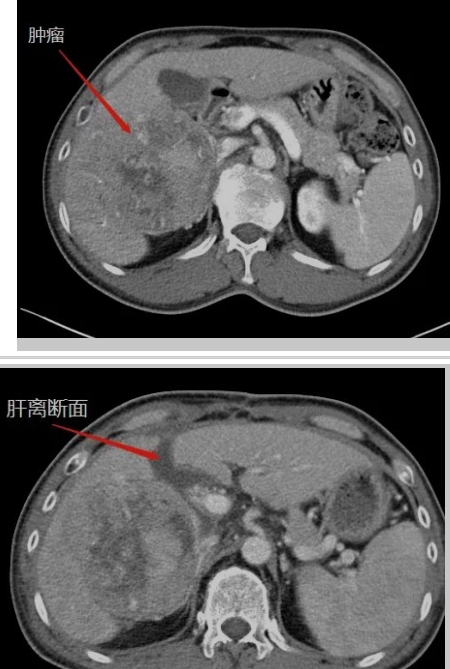

在生命的長河中,每個人都在與時間賽跑,與命運抗爭。而對王晚期肝癌患者來說,這場賽跑尤為艱難,這場抗爭格外驚心動魄。還記得四年半以前,當40多歲的王先生被確診為晚期肝癌伴乙肝、肝硬化時,絕望的陰霾籠罩著整個家庭。對王先生來說,那是一段黑暗的日子,對未來的恐懼,對生命的不舍,尤其對年幼的孩子的不舍,讓他...